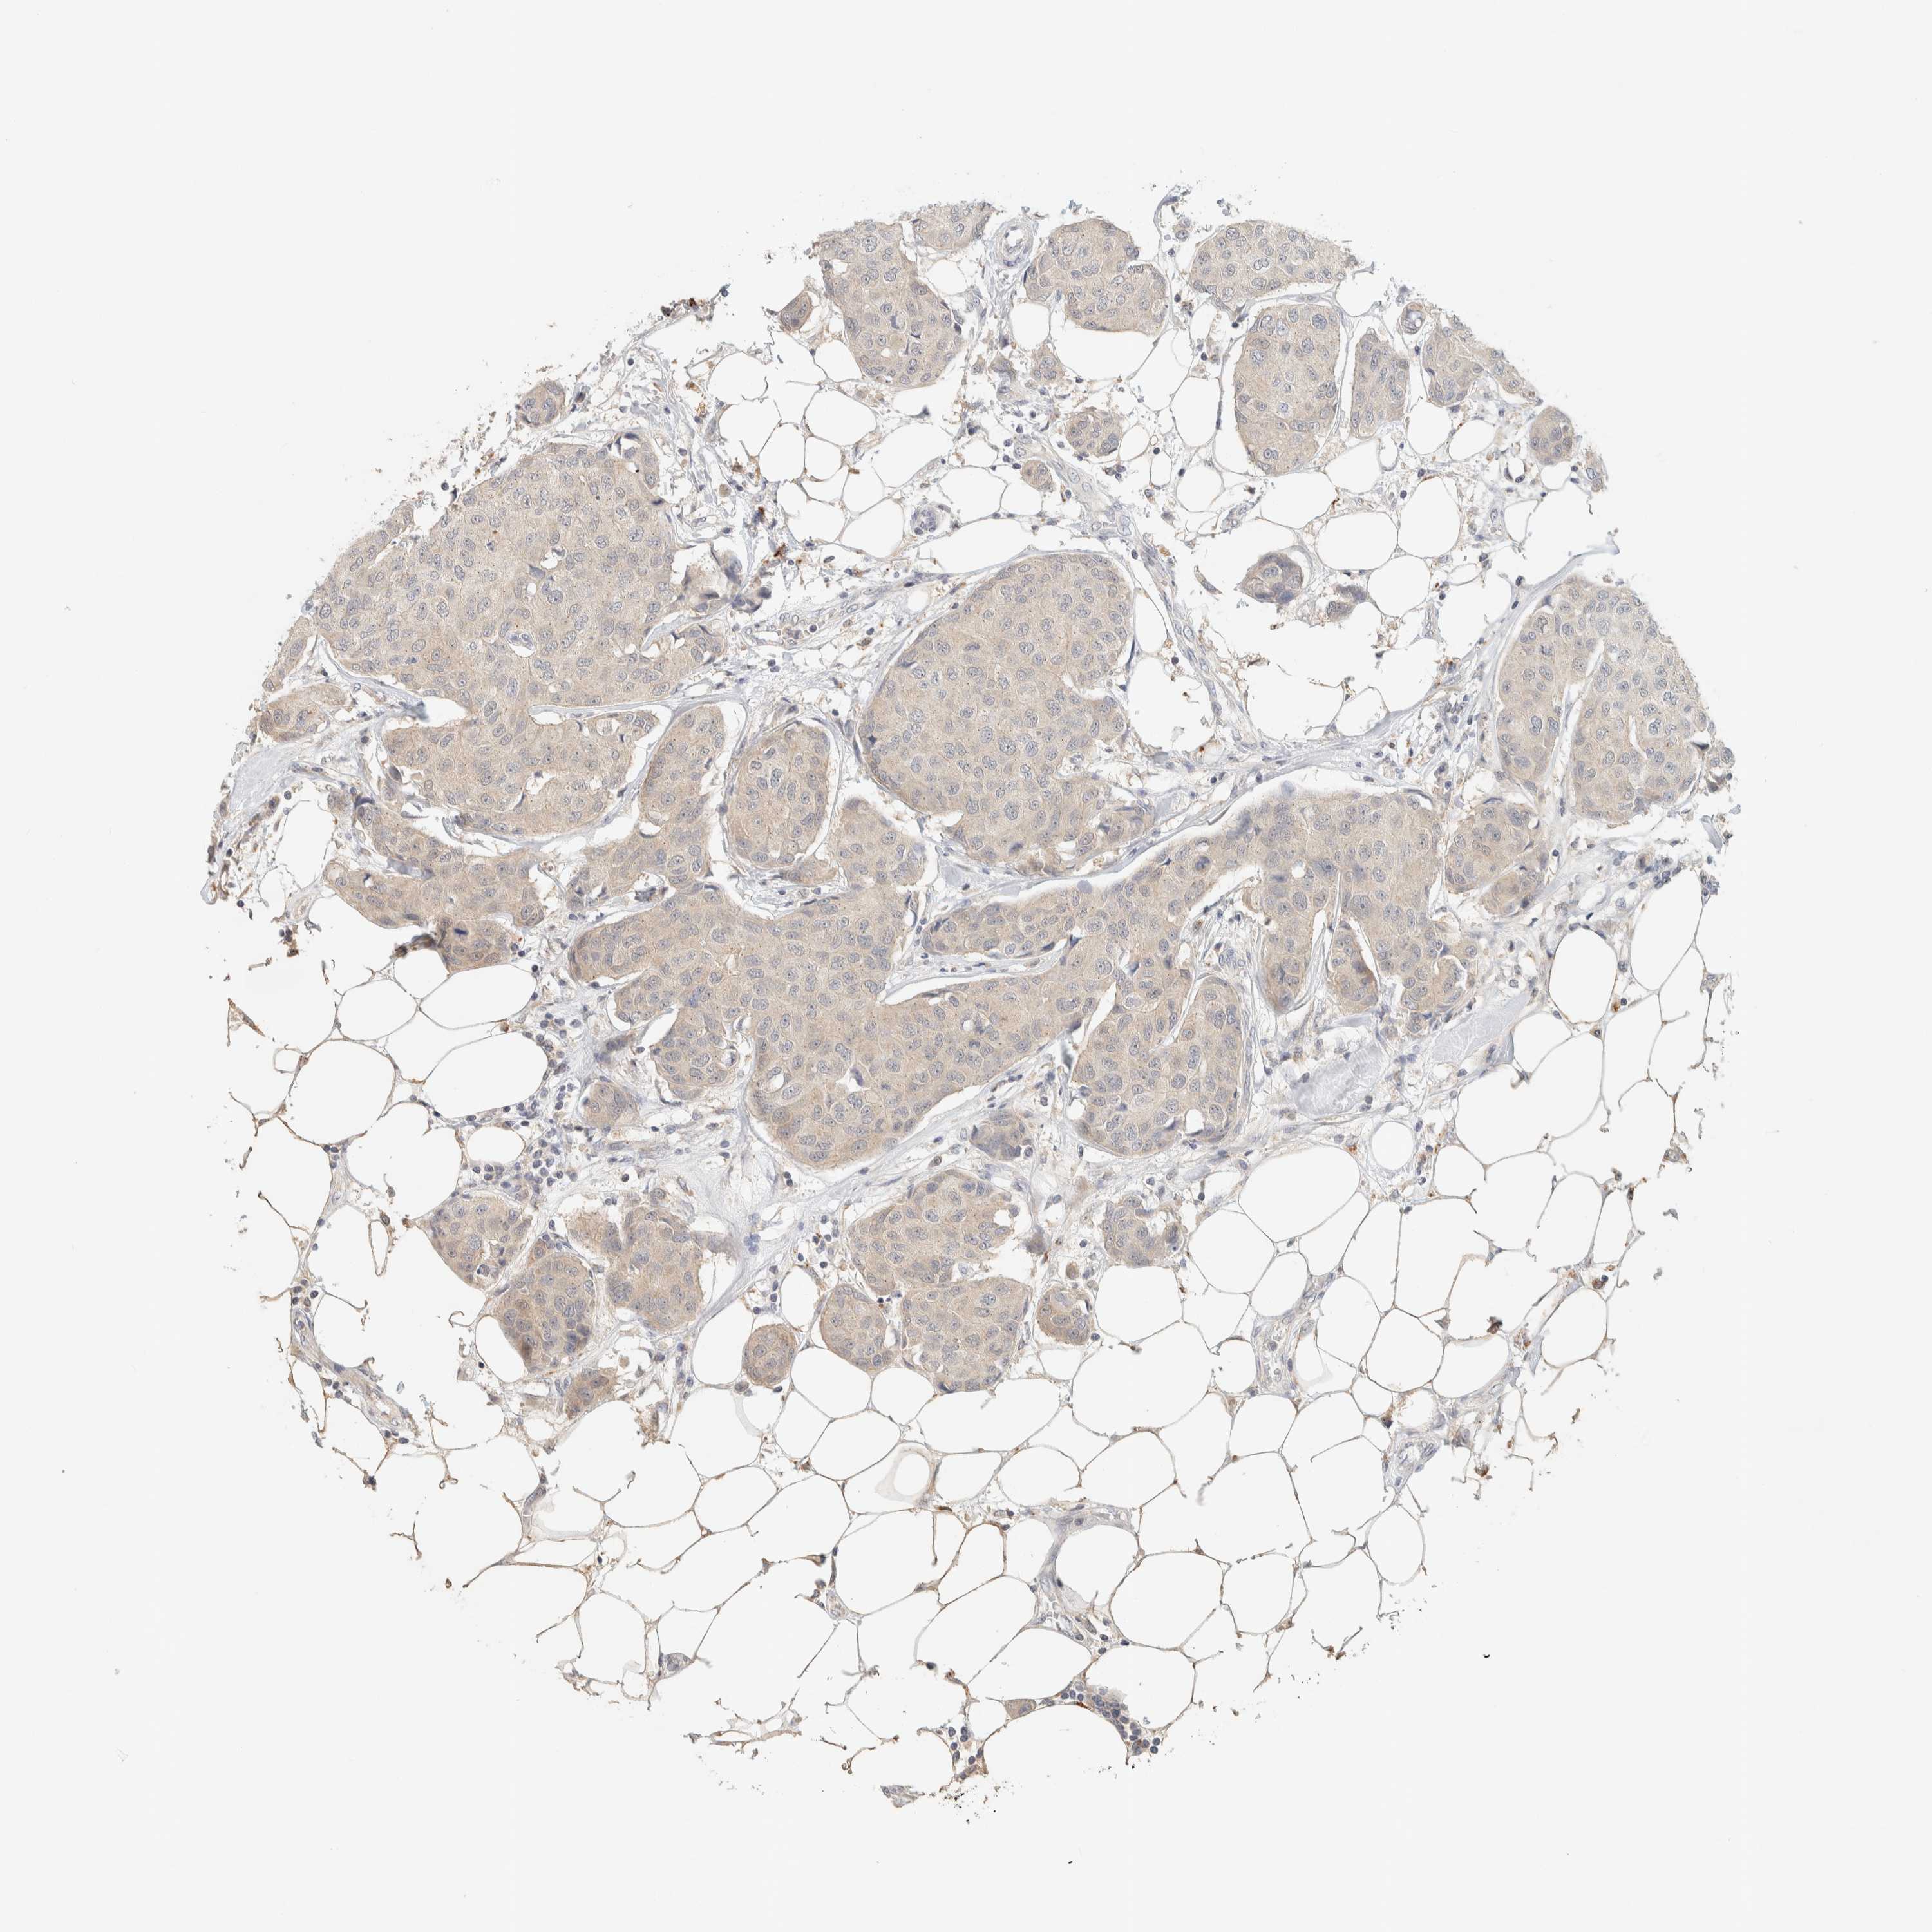

BRCA TCGA BRCA VALIDATION PROTEIN EXPRESSION

ANTIBODIES

AND

VALIDATION